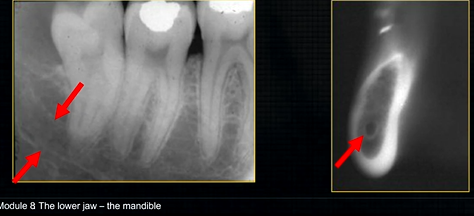

mental foramen - black radiolucency - near 1st and 2nd premolars

sockets of the teeth are represented by thin, white, opaque lines → ‘ lamina dura’

dense, white, radiopaque line → dense bone of mylohyoid ridge

underneath mylohyoid ridge - looks more radiolucent → this is due to the lingual indentation of submandibular fossa

dense cortical bone of the lower border

inferior dental canal can easily be seen in cross sectional dental images